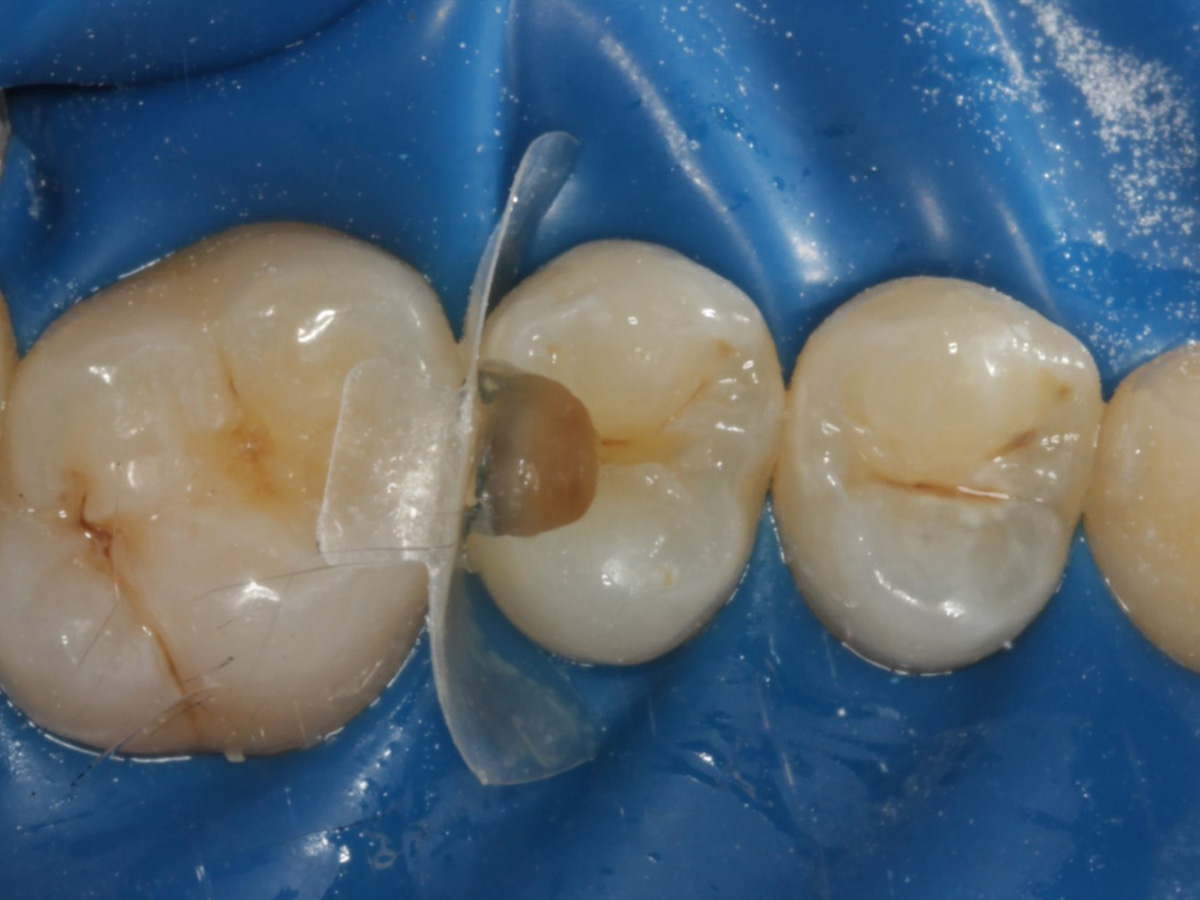

Behandlung einer tiefreichenden Karies an Zahn 25 distal

Tiefreichende kariöse Läsionen im distalen Bereich stellen häufig eine besondere Herausforderung dar, da sie sowohl eine präzise Kavitätenpräparation als auch eine anspruchsvolle Rekonstruktion der Kontaktpunkte erfordern. Durch Anwendung der Bioclear Evolve Matrizen konnten in diesem Fall eine ästhetisch und funktionell hochwertige Versorgung erzielt werden, die gleichzeitig minimalinvasiv und substanzschonend war.

Abbildung 1

Approximalraumkaries an Zahn 25 distal

Schutz des Nachbarzahnes und des Kofferdams mit wiederverwandter Bioclear Biofit Matrize (gereinigt und sterilisiert); Separation zur Applikation der Matrize mit Heidemannspatel

Abbildung 5

Defektdarstellung